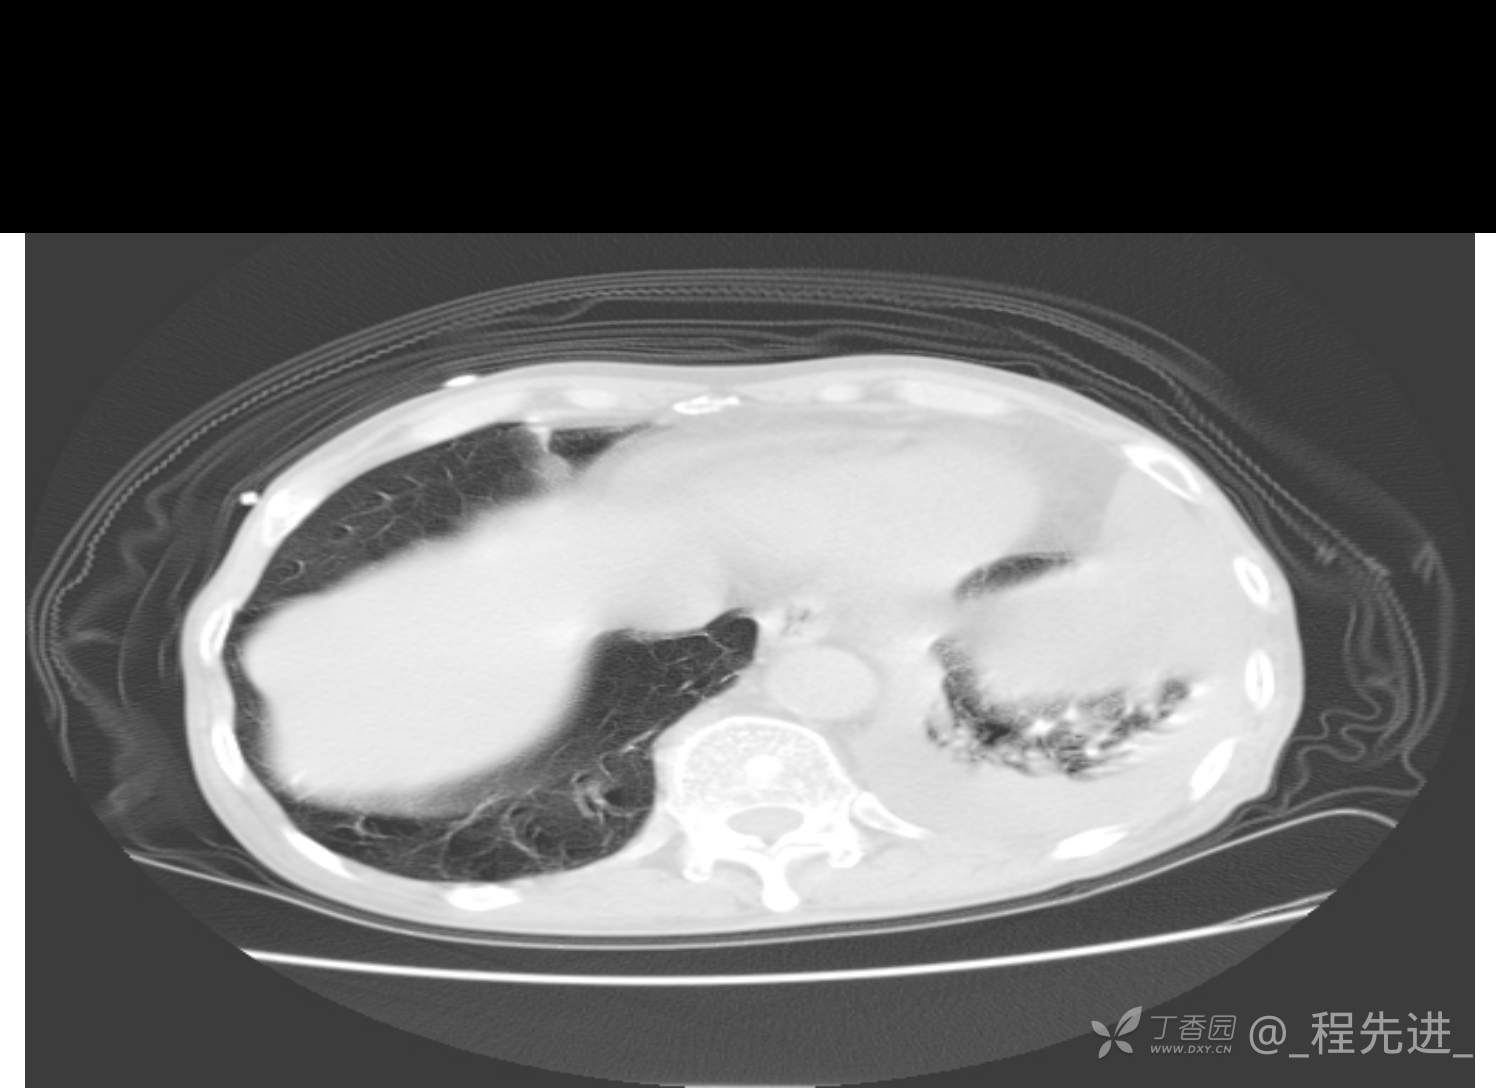

患者性别:男

患者年龄:81岁

简要病史:反复咳嗽、咳痰20余年,加重1周。两肺呼吸音低,可闻及散在干湿啰音。